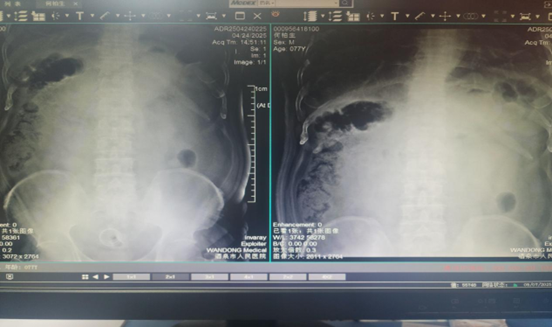

近日,我院胃腸專(zhuān)科接診了一位77歲老年患者,患者半月前確診乙狀結(jié)腸惡性腫瘤并狹窄,近3天突感腹痛腹脹,伴惡心、嘔吐、排便不暢。腹部立位平片及腹部CT示為急性腸梗阻,針對(duì)患者高齡,梗阻癥狀嚴(yán)重等實(shí)際情況,科室副主任醫(yī)師王曉輝建議為患者行“可過(guò)活檢孔道腸道支架置入術(shù)”。經(jīng)過(guò)完善的術(shù)前檢查,在直乙狀結(jié)腸近乎完全梗阻的情況下,手術(shù)團(tuán)隊(duì)在可視化腸道鉗道下成功置入支架,手術(shù)全程30分鐘左右,術(shù)后復(fù)查腹平片確認(rèn)腸道支架位置良好,未見(jiàn)脫落,患者排便順利,效果立竿見(jiàn)影,患者及家屬非常滿(mǎn)意手術(shù)效果。

術(shù)前